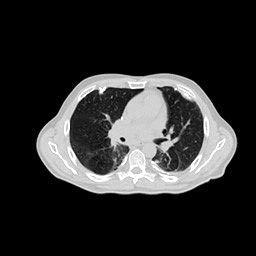

4.3 Few-View CT Reconstruction

In this section, the reconstruction performance of our proposed framework under few-view conditions will be tested. For the parallel-beam and fan-beam geometry, the number of views increases from to , uniformly distributing from to and to respectively. Such settings provide a complete benchmark of reconstruction performance, ranging from extremely sparse to relatively complete, full-view CT reconstruction. The experiment results are shown in Fig.5. Additionally, the ground truth, few-view ( views), and full-view ( views) CT reconstruction results of different methods are shown in the first and third rows of Fig.7 (parallel-beam, LIDC-IDRI dataset), and Fig.8 (fan-beam, LIDC-IDRI dataset).

(a) Ground Truth

43.87dB

(b) ASD-POCS

47.96dB

(c) RBP-DIP

34.46dB

(d) DIP

26.63dB

(e) MED50

29.03dB

(f) RED-CNN

Conventional IR methods, even those with the help of regularizations such as total variation, are prone to artifacts when constrained by few-view and limited-angle conditions. However, as illustrated in the first and second rows of Fig.7b, and Fig.8b, these images still contain meaningful information which can be used to guide DIP related reconstruction methods, despite the presence of artifacts.

DIP related methods, which leverage the hierarchical structure of neural networks as a powerful prior, can better handle the aforementioned challenge. However, the original DIP method has its own limitations. It cannot generate detailed images or effectively enhance its accuracy as the number of measurements increases. For instance, in Fig.5a, the ASD-POCS algorithm achieves an approximate SNR gain of dB when the number of views increases from to , while the DIP method only attains an approximate dB gain. This problem is also shown in the last row of Fig.7, and Fig.8. Moreover, the DIP method may produce neural network specific artifacts, as shown in Fig.7d, and Fig.8d. These artifacts are particularly problematic as they are often considered more undesirable than streak artifacts. Radiologists, with their professional experience, can interpret and account for streak artifacts, whereas network specific artifacts may prove more challenging to identify and address.

The proposed RBP-DIP framework combines the two approaches utilizing the newly devised RBP connection so that inherits the benefits of both methods. In Fig.4, the RBP-DIP method’s attainment of a 5dB SNR enhancement over the ASD-POCS method, despite exhibiting a larger loss, underscores the potency of the DIP. Subsequently, the improvement surpassing the original DIP method indicates the efficacy of the RBP connection. Moreover, by employing the RBP connection, neural network specific artifacts can be rectified effectively. As a result, substantial advancements can be shown in Fig.5, Fig.6, Fig.7, and Fig.8.